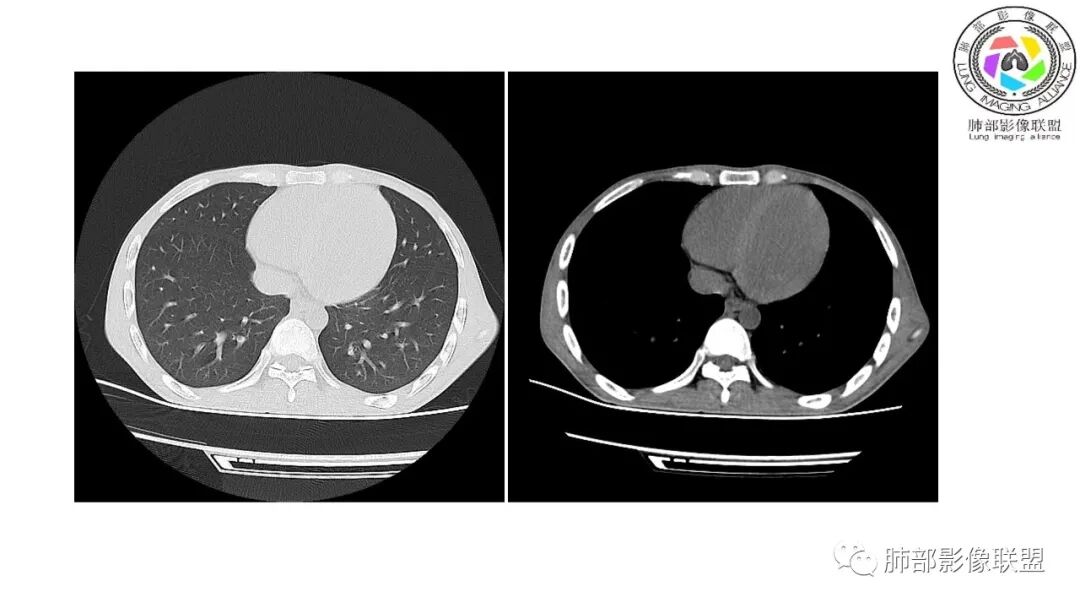

影像与临床:1.青年男性,HlV阳性,颜面部皮疹(未提供皮疹图像)、发热(高热),实验室CRP、PCT高,T-Spot阴性。2.右肺下叶空洞结节,壁厚不均,边界清楚,其内线状影,未见液平及钙化,未见卫星灶,纵隔淋巴结增大,双侧腋窝见增大淋巴结。心腔内低密度提示贫血可能。肝脾影增大,未见结节影及块影。腹膜后见多发增大淋巴结。

综合分析:本例肺部影像学改变并不具有特征性,空洞性病灶须与多种疾病鉴别,但年轻HIV阳性患者,高热,皮疹,肝脾增大,纵隔、腋窝、腹膜后见多发增大淋巴结等都强烈提示马尔尼菲篮状菌感染的可能性。

宇宙:青年男性,HlV阳性,皮疹、发热,实验室CRP、PCT高,结核阴性,右肺下叶薄壁空洞结节,其内线状影,纵隔淋巴结稍大,心腔密度低,腹腔多发肿大淋巴结,支持马尼

丽:青年男性,发热伴皮疹,右肺下叶空洞型病变,呈薄壁,内丝丝缕缕不干净,伴腹腔及腹膜后多发肿大淋巴结,治疗后右肺下叶空洞无明显好转,贫血,考虑马尼